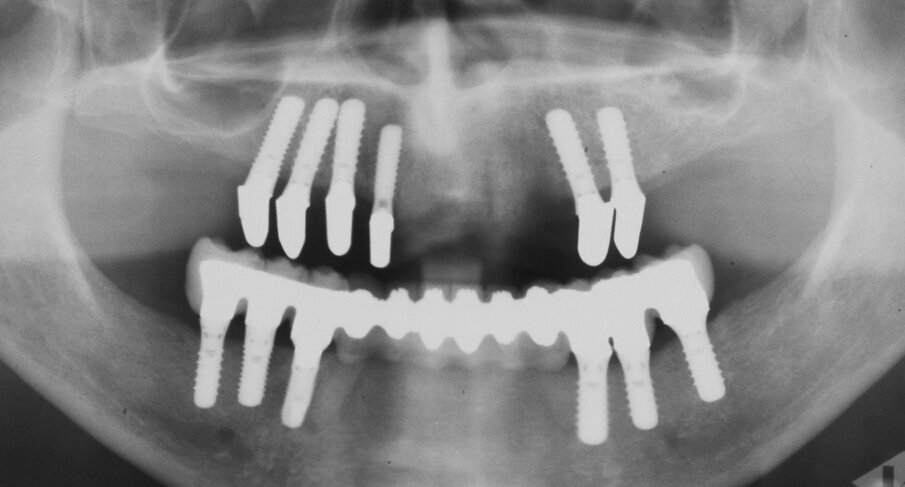

One year later, the patient presented again for consultation. Eleven implants have been placed (#12-15, 24, 25, 36-34, 45 and 46) and the maxilla and mandible have been restored with FPDs at the patient’s request (Fig. 3 – Fig. 5). However, the patient was dissatisfied with the esthetic results due to the unnatural length of the artificial teeth. Furthermore, the design of the existing FPDs impeded oral hygiene.

Fig. 3. 2nd consultation. Orthopantomograph. After implant placement and prosthetic treatment.